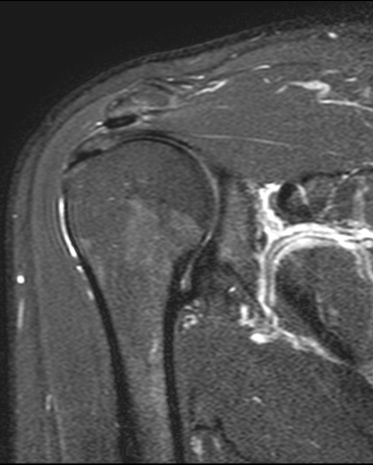

3. MRI检查:MRI在神经系统疾病的诊断中优势显著,对于脑肿瘤、脑梗死、脊髓病变等的诊断准确性较高。例如,对于一些早期的脑肿瘤,MRI能够更清晰地显示肿瘤的位置、大小、范围以及与周围组织的关系,有助于制定治疗方案。在关节疾病方面,MRI可以清晰地显示关节软骨、半月板、韧带等软组织的损伤情况,对于膝关节半月板损伤、交叉韧带断裂、肩关节肩袖损伤等疾病的诊断具有重要价值。此外,MRI在乳腺疾病、盆腔疾病等方面也有广泛的应用。

脑肿瘤T1WI+C、右膝外侧半月板撕裂、右侧膝前交叉韧带断裂、右侧肩袖损伤